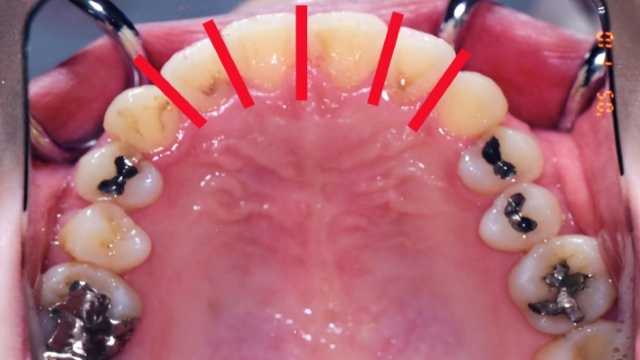

一般的には、犬歯から犬歯までの「前歯6本」、あるいはさらに範囲を絞った数本を対象とします。

リスク1:無理やり並べると「出っ歯」になる可能性あり

これが最も多いトラブルの一つです。

ガタガタの歯並び(叢生:そうせい)は、顎の骨のスペースに対して歯が並びきらない「定員オーバー」の状態です。

4人掛けのベンチに無理やり5人が座ろうとしている状態を想像してください。誰かが前に飛び出すか、後ろに下がるしかありません。

この状態で、抜歯や奥歯の移動を行わずに無理やり前歯だけを一列に並べようとするとどうなるでしょうか? 前歯を前方に広げるしかありません。

その結果、歯並び自体は真っ直ぐになっても、歯列全体が前方に飛び出し、口元が盛り上がった「口ゴボ(出っ歯)」になってしまいます。

「歯並びは良くなったけれど、口が閉じにくくなった」「横顔が以前より不格好になった」という失敗例の多くは、この無理な拡大が原因です。